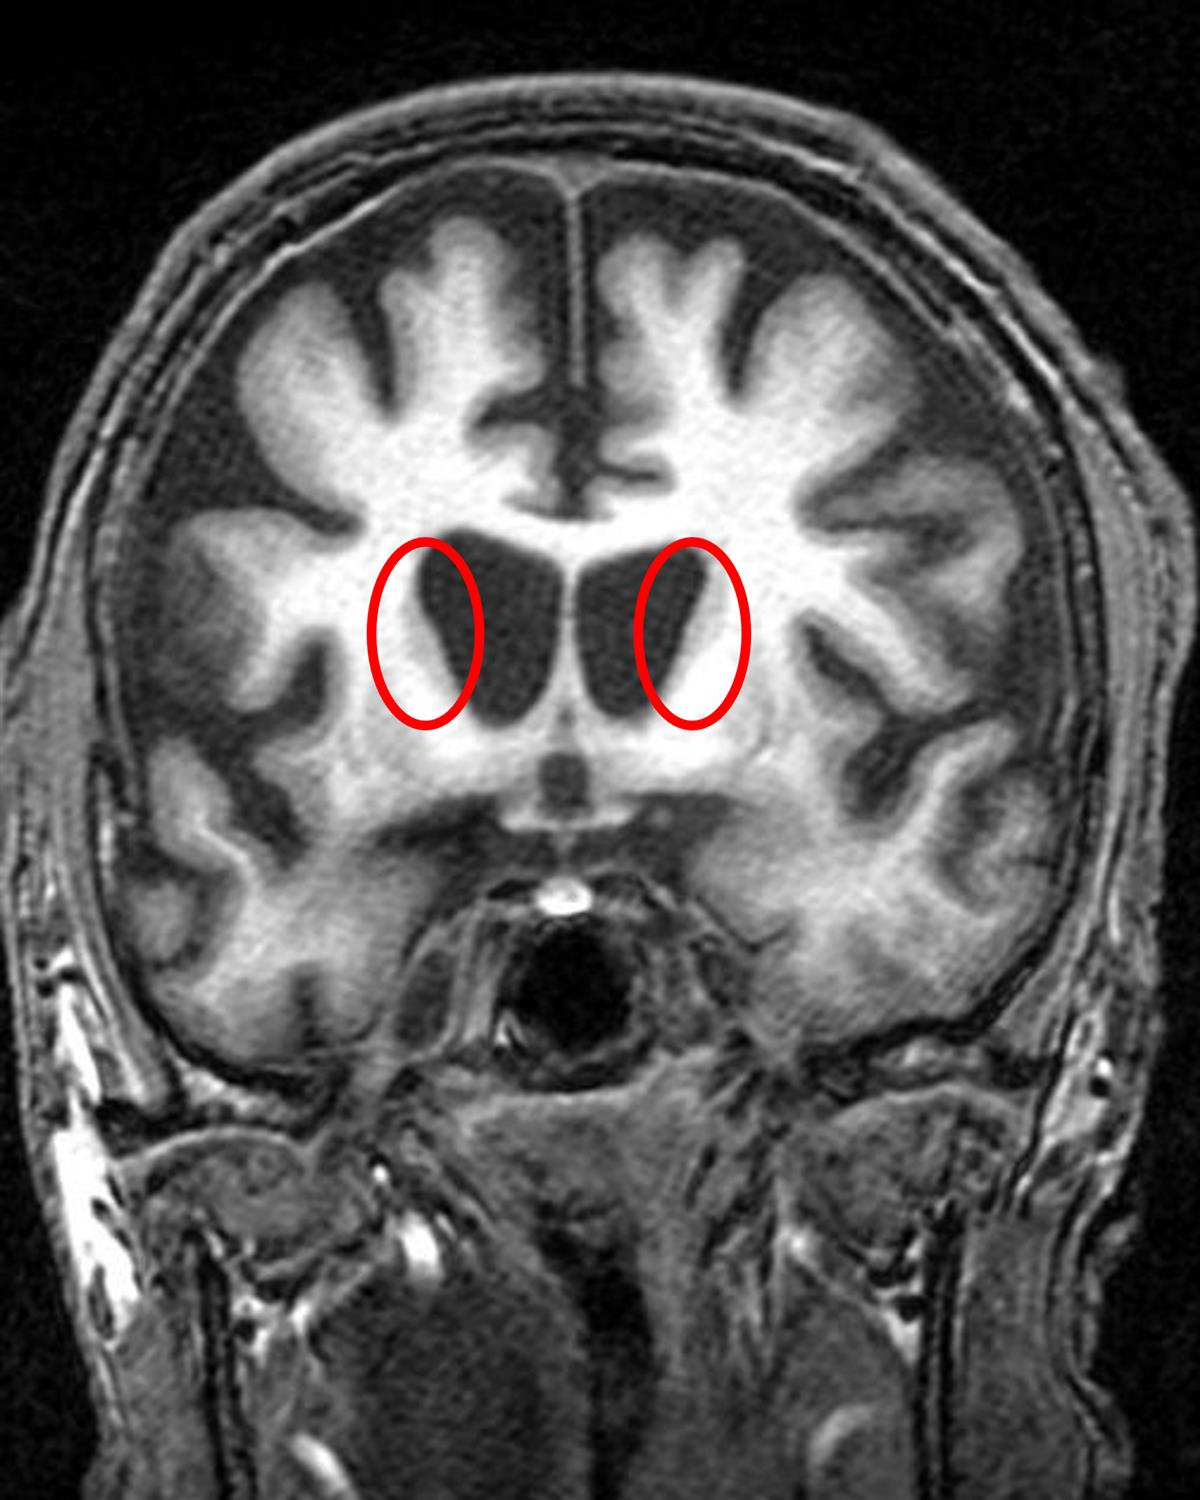

A 51-year-old man presents to his primary care physician with a 3 month history of motor difficulties. He first noticed that he was dropping items occasionally but this has progressed to impairing daily activities. His wife has also noticed that he makes writhing movements with his arms when he is distracted and that he has become more irritable and less interactive with his family and friends. He has a medical history of hypertension and hyperlipidemia for which he takes lisinopril and simvastatin. His temperature is 98.6°F (37°C), blood pressure is 135/74 mmHg, pulse is 85/min, respirations are 14/min, and oxygen saturation is 98% on room air. A neurological examination is remarkable for involuntary movements affecting his bilateral upper extremities. He appears apathetic and has impaired organization and planning on cognitive testing. An MRI of his brain is demonstrated in Figure A. Which of the following is the most likely cause of this patient's symptoms?

This patient with chorea-like movements, mood disturbances, impaired executive function, and caudate atrophy on MRI, most likely has Huntington disease. Huntington disease is caused by a CAG trinucleotide expansion on chromosome 4.

Figure/Illustration A is a coronal MRI that demonstrates prominent caudate atrophy (red circle). This finding is characteristically seen in a patient with Huntington disease.